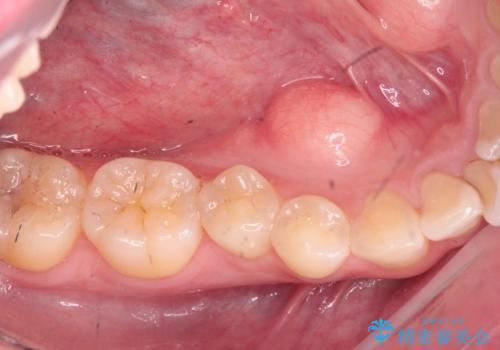

- マウスピース矯正を行うにあたり、舌のスペースが狭くなってしまうことから骨隆起の除去を希望されました。

反対側も除去を予定しています。